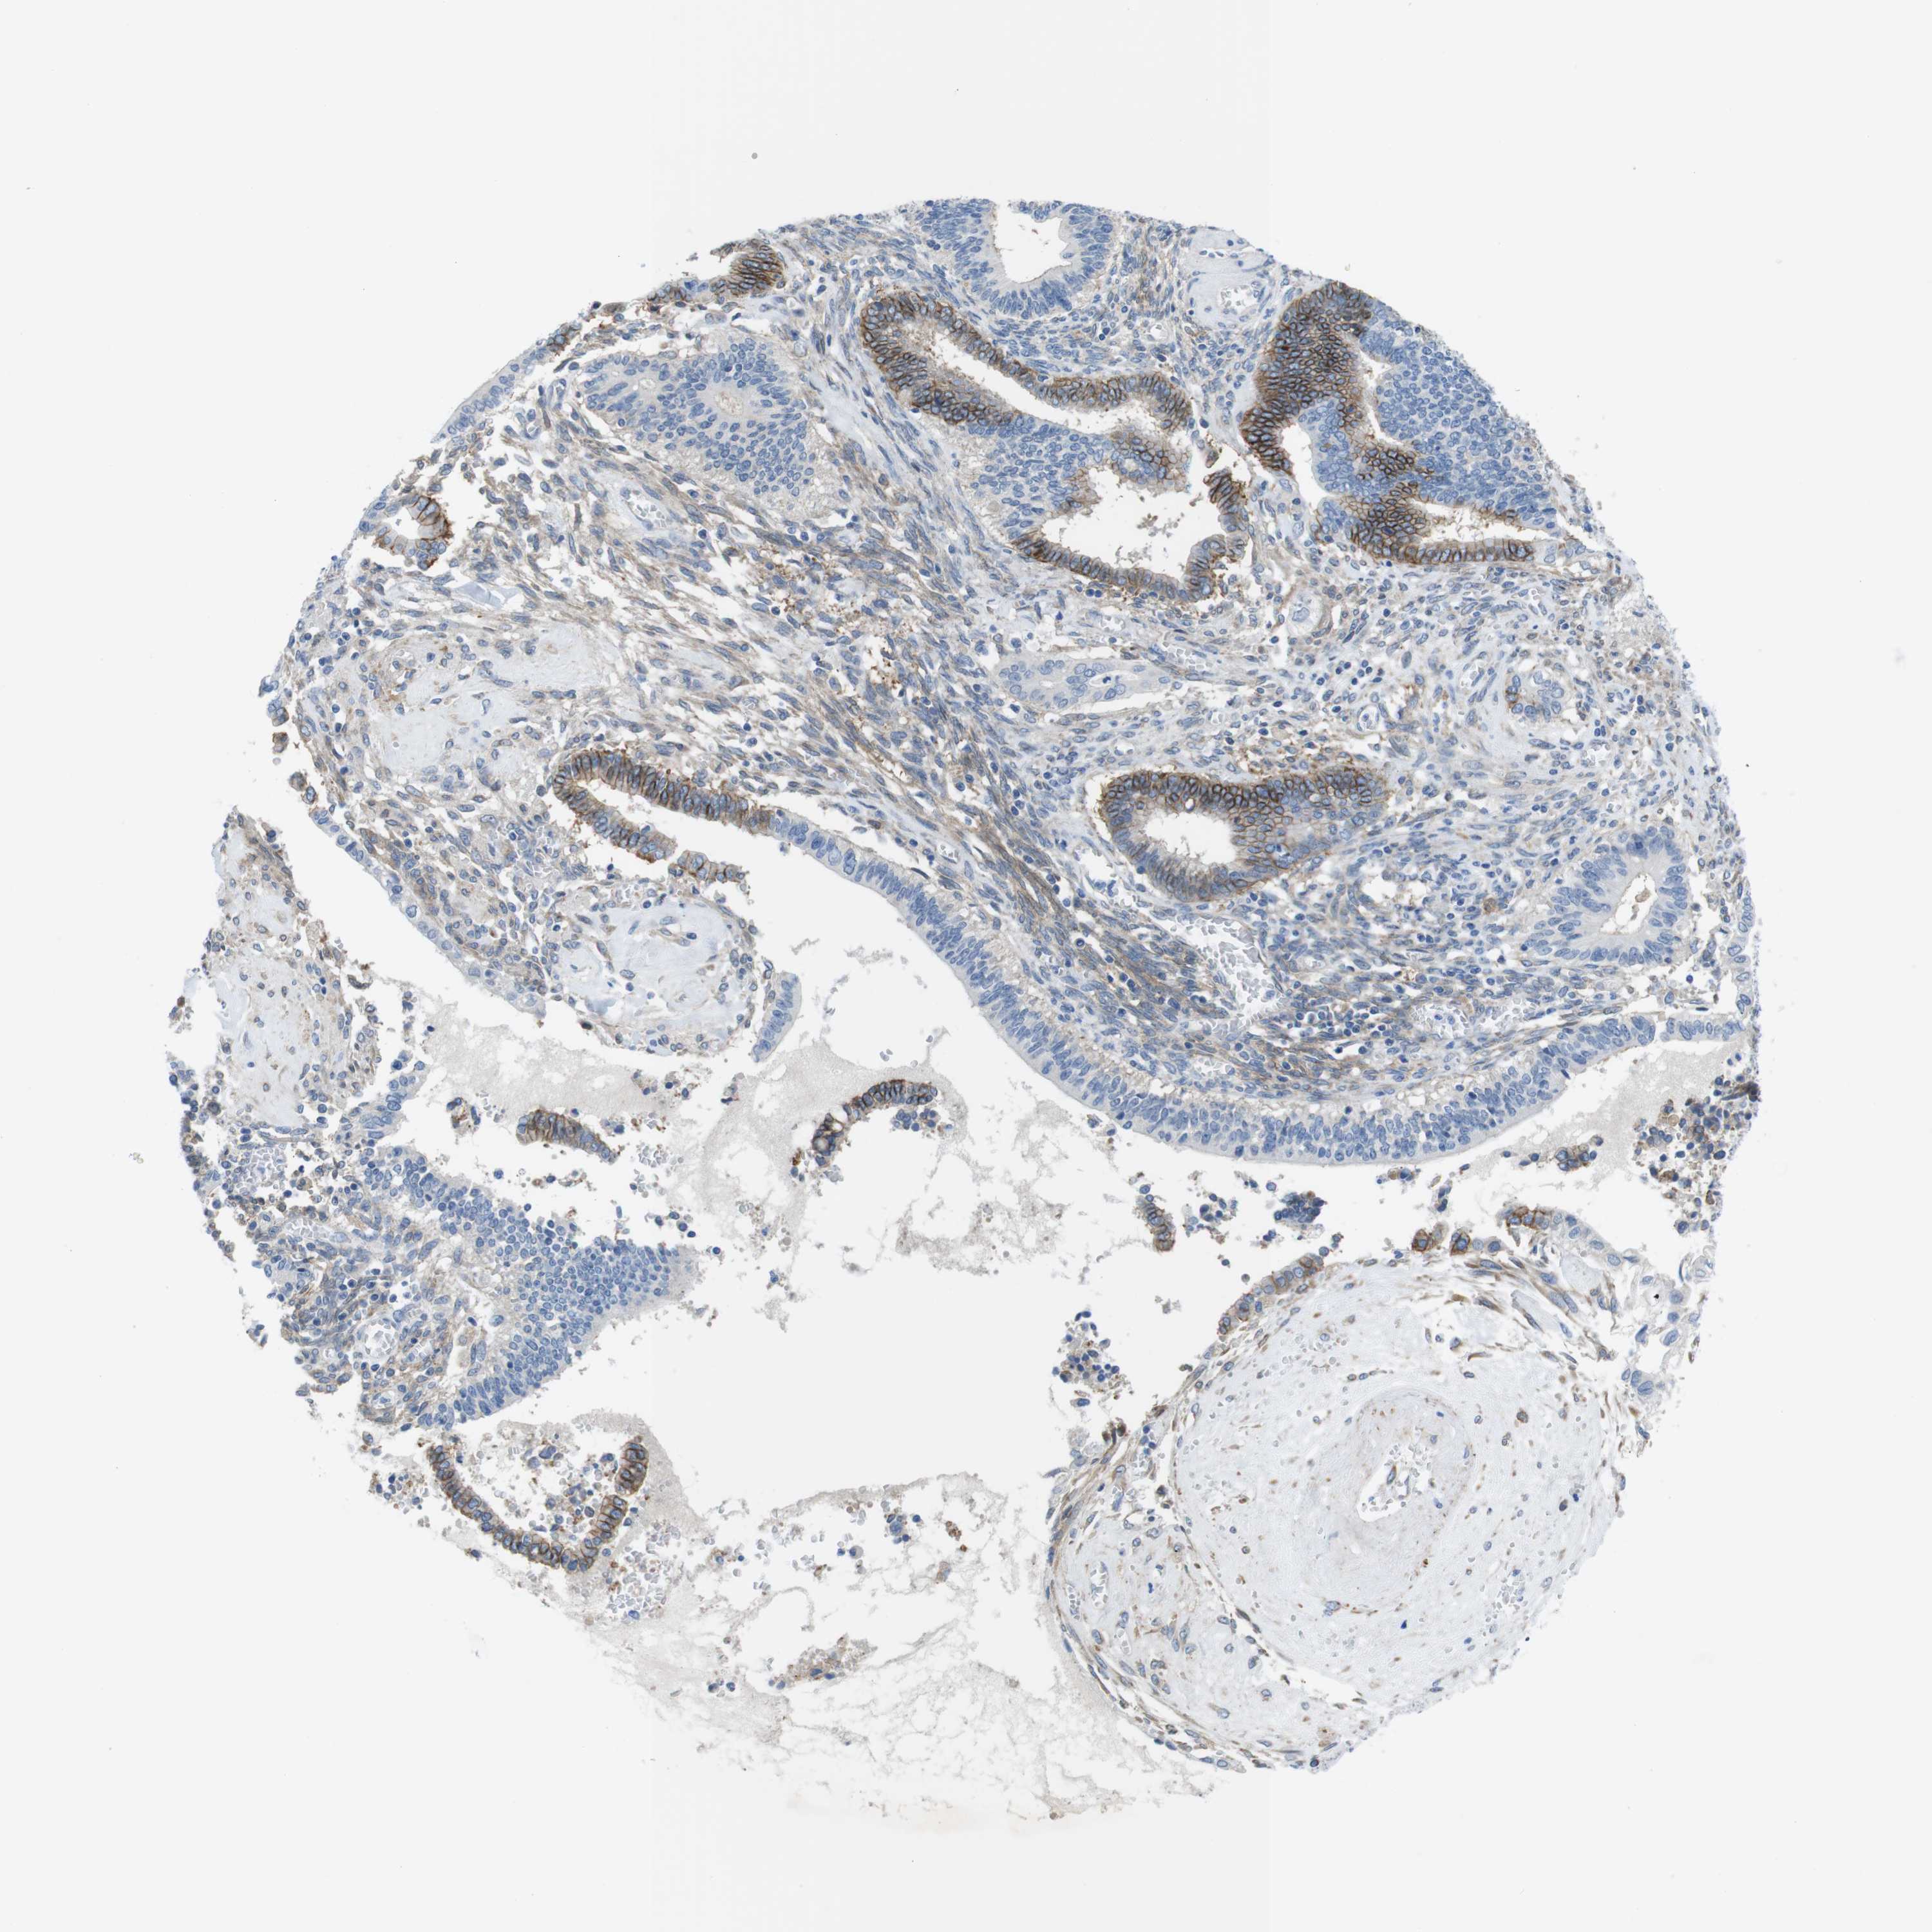

CERVICAL CANCER - Protein expressioni

A mouse-over function shows sample information and annotation data. Click on an image to view it in a full screen mode. Samples can be filtered based on level of antibody staining by selecting one or several of the following categories: high, medium, low and not detected. The assay and annotation is described here.

Note that samples used for immunohistochemistry by the Human Protein Atlas do not correspond to samples in the TCGA dataset.

Antibody stainingi

Antibody staining in the annotated cell types in the current human tissue is reported as not detected, low, medium, or high, based on conventional immunohistochemistry profiling in selected tissues. This score is based on the combination of the staining intensity and fraction of stained cells.

Each image is clickable and will lead to virtual microscopy that enables deeper exploration of all samples and also displays staining intensity scores, fraction scores and subcellular localization as well as patient and tissue information for each sample.

Antibody HPA014908

Staining

High

Medium

Low

Not detected

Intensity

Strong

Moderate

Weak

Negative

Quantity

>75%

75%-25%

<25%

None

Location

Nuclear

Cytoplasmic/membranous

Cytoplasmic/membranous,nuclear

Squamous cell carcinoma, NOS

Adenocarcinoma, NOS